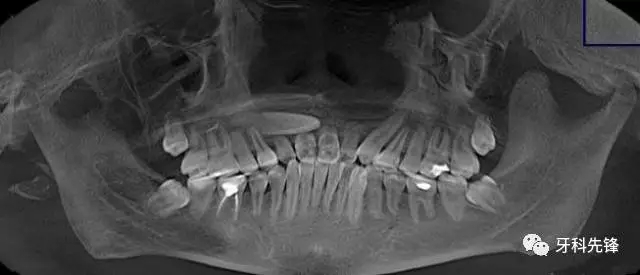

圖2.術(shù)前的CBCT檢查:11牙根幾乎完全吸收、12牙根吸收2/3. 21牙齒唇側(cè)牙根部分吸收。